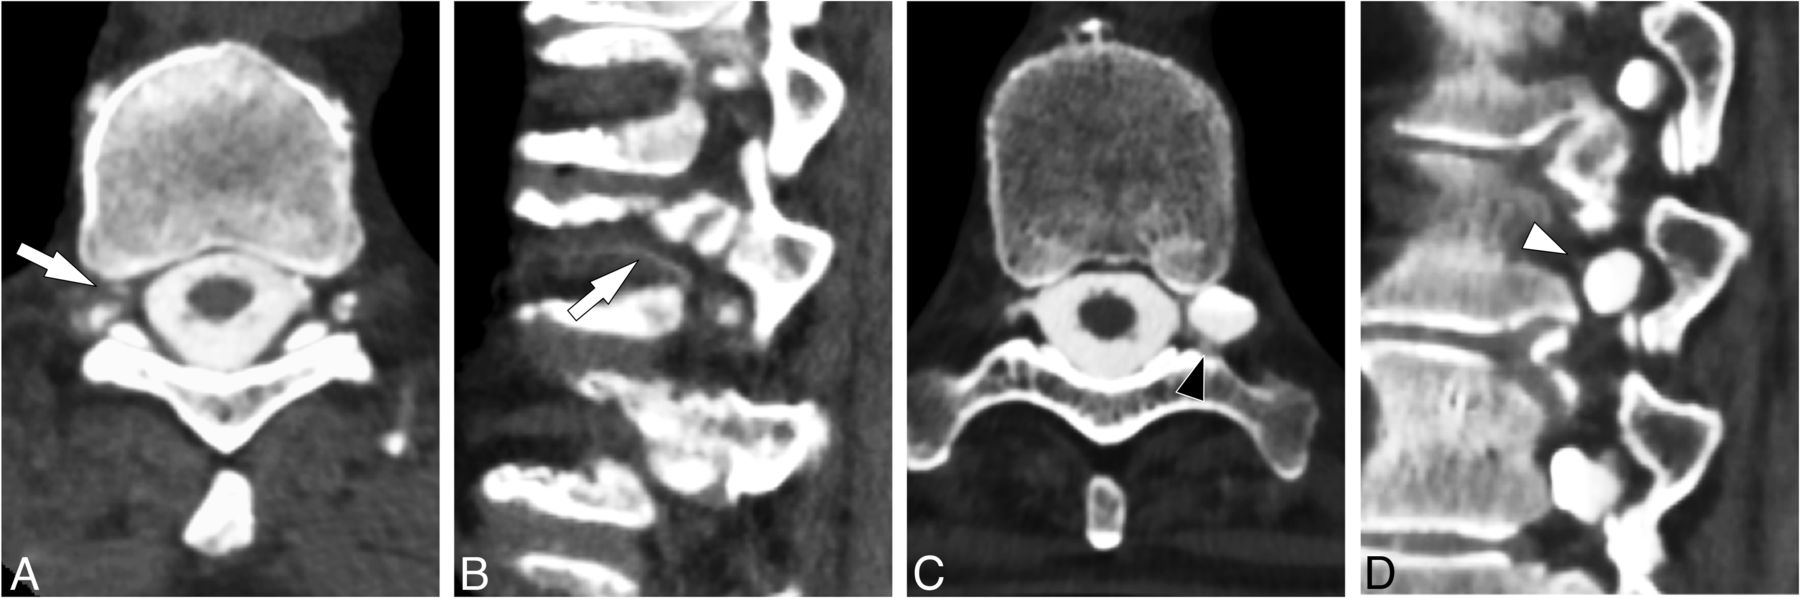

CT myelograms were reviewed to determine the presence of a CVF. Assessment was based on the presence of a “hyperdense paraspinal vein” sign and was performed by 1 of 2 study neuroradiologists with 12–15 years’ experience evaluating CTM for SIH (Fig 2).11 In equivocal cases, the imaging was jointly reviewed by both neuroradiologists to reach a consensus (Fig 3).

Examples of CVFs seen on CTM. Axial image from CTM obtained with the patient in the right lateral decubitus position (A) shows venous contrast opacification, indicating the presence of a CVF in a segmental spinal vein (white arrow). Axial image from CTM performed with the patient in the prone position (B) shows contrast opacification of the internal epidural venous plexus within the spinal canal (white arrow), also diagnostic of a CVF.